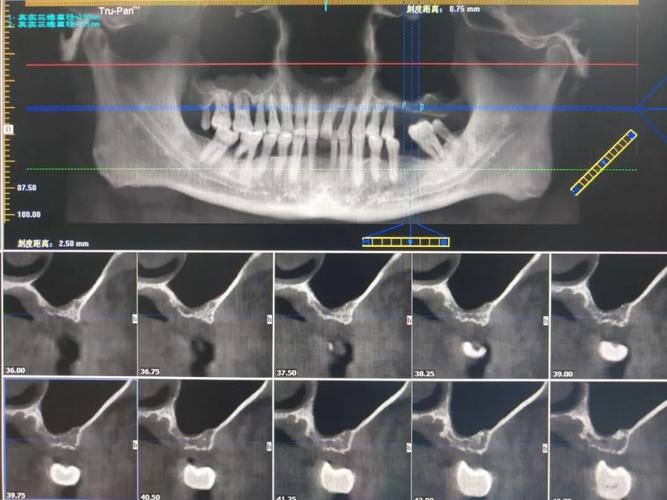

锥形束CT(CBCT)的普及与标准化应用:

- 核心进展: CBCT已成为评估上颌窦与牙根关系的金标准,它提供三维立体图像,清晰显示:

- 上颌窦底形态(平坦、凹陷、气化程度)。

- 牙根与窦底的距离(关键指标)。

- 牙根是否已穿入窦腔(穿孔大小、位置)。

- 窦内粘膜厚度、是否有炎症或囊肿。

- 骨量评估(种植或正畸移动所需)。

- 定量分析: 开发软件自动测量骨厚度、窦底最低点位置、牙根-窦底距离等参数,建立风险预测模型。

- 动态评估: 利用CBCT追踪正畸移动过程中牙根位置的变化和骨改建情况。